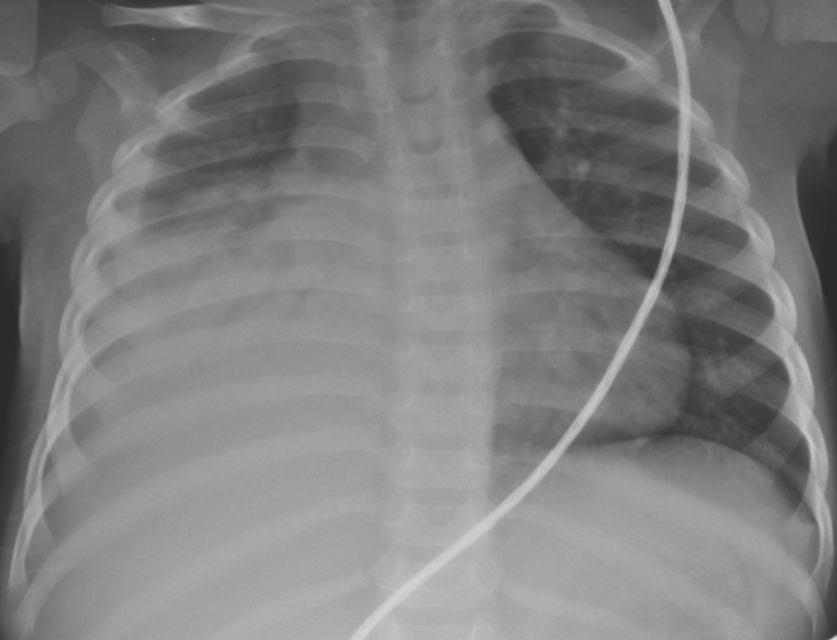

Mairelys Gonzalez, MD; Joanne Holliman, MD; Betzi Teran, MD; Yekaterina Sitniskaya, MD; Elita Gose-Balakrishnan, MD; Magda Mendez, MD, FAAP

A 19-month-old boy known to have intermittent asthma and a history of prior right lower-lobe pneumonia presented to the emergency department (ED) with a 1-week history of cough, runny nose, chest...